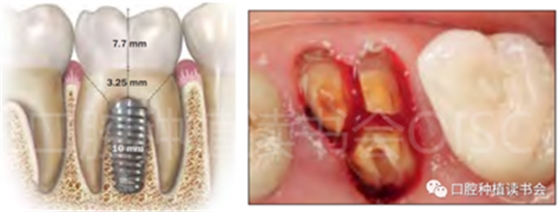

(5)可以有效的關閉拔牙創(chuàng)(圖2、圖3)。

圖2 初期穩(wěn)定性良好的位點,采用愈合基臺+縫合固定的方法關閉拔牙創(chuàng),術后1周獲得良好的軟組織愈合。

圖3 初期穩(wěn)定性不足的位點,采用膠原蛋白覆蓋(倍菱)+縫合固定的方法關閉拔牙創(chuàng),術后10天獲得良好的軟組織愈合。